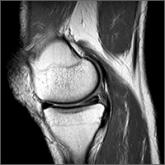

ArticleManaging atraumatic meniscal tears in middle-aged patientsAuthor:Jeremy Korsh, MDPublish date: November 1, 2017What role does arthroscopic surgery have in the treatment of patients with atraumatic meniscal tears and osteoarthritis? The authors reviewed the l...Read More